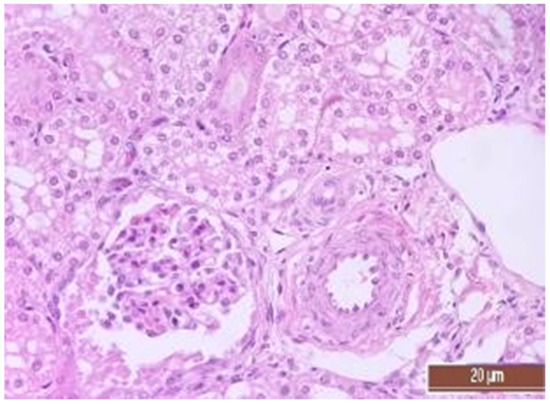

3.4. Pathology of Kidneys